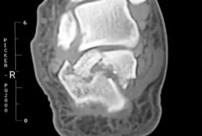

跟骨骨折冠状面影像

当跌倒后出现足后跟剧烈疼痛,局部肿胀及瘀斑明显,跟骨压痛,无法下地行走,应高度怀疑跟骨骨折,要马上到医院确诊(拍X光片,跟骨正侧位+轴位片)。针对严重的粉碎性或者波及关节面的骨折,最好还要做个CT,指导具体手术方案。

足部的骨骼结构复杂,这使跟骨骨折的复位,变得有难度。首先跟骨与3个关节面连接,包括前距关节面,中距关节面,和后距关节面;这三个关节面分别与前跟、中跟、后跟组合成了距下关节。再者,跟骨与多条韧带相连,包括跟腓韧带等。